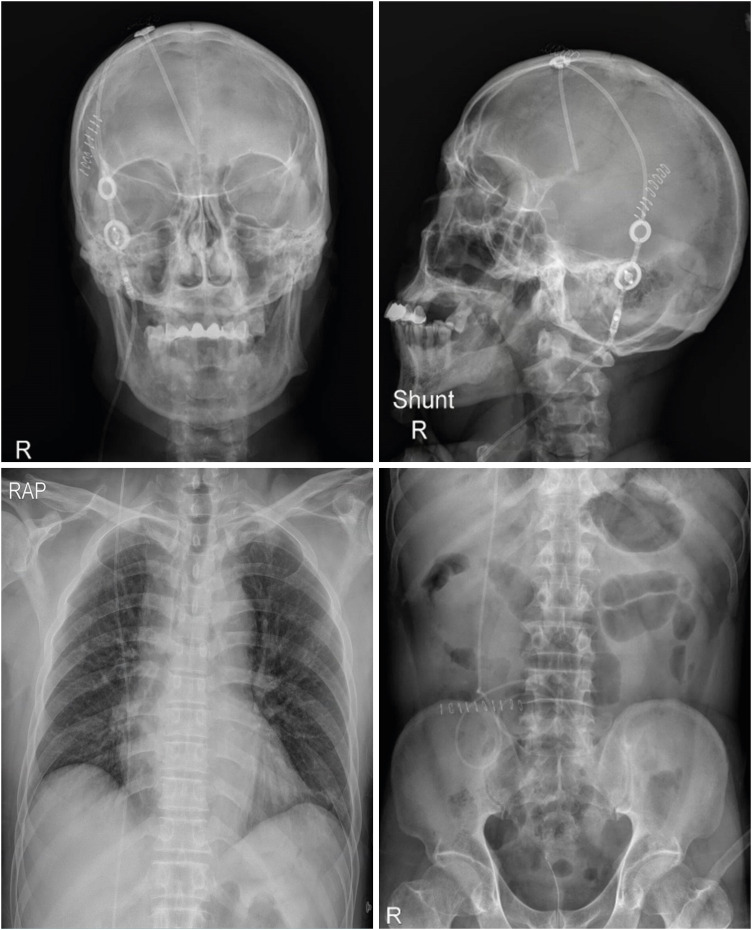

The treatment of hydrocephalus with a ventriculoperitoneal (VP) shunt can lead to complications such as shunt migration. A 67-year-old male, who had previously undergone VP shunt surgery for normal-pressure hydrocephalus, presented approximately five years later with symptoms of general weakness and abdominal pain. Imaging revealed shunt malpositioning, with the catheter passing through an abnormal route to the heart. The catheter was successfully removed under fluoroscopic guidance while monitoring patient's electrocardiogram to prevent potential secondary complications. Although rare, cardiac migration of VP shunts can lead to life-threatening secondary complications. Our case highlights the possibility of delayed upward migration of the shunt catheter in patients with VP shunts, emphasizing the need for various strategies to address and manage this issue.

Abstract Image